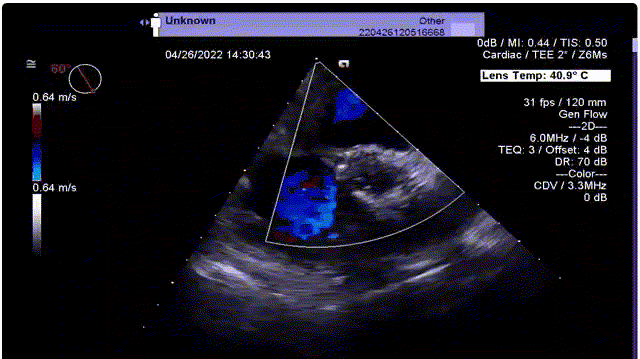

超声下血流动力学良好,无反流

术前V-max从4.1m/s下降至2m/s,PG 68mmHg下降至16.86mmHg。